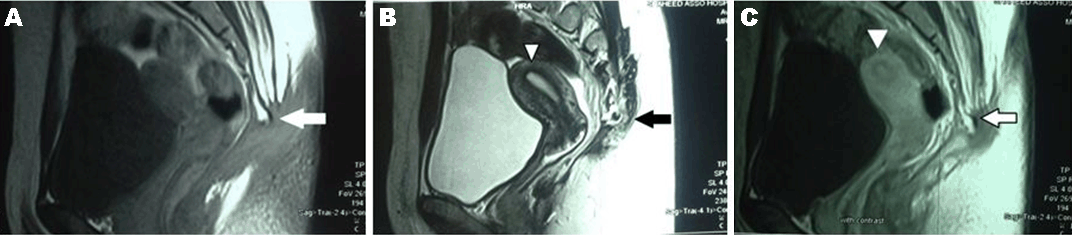

Case 1 History and Examination The patient had a history of a small bulge in the perineum on the right side and a small sinus just below her coccyx during her lifetime. She had no leg pain or paresthesias, no difficulties in urination or defecation, no weight loss, and was able to walk with no difficulties. The patient had an uneventful medical and surgical history with a negative parental consanguinity and a negative family history for same. No irregularities were marked in the menstrual cycle since her menarche at 12 years. In the last two years, she had a decrease in the duration of bleeding (from seven to three days) but with a normal amount of flow. On physical examination, lower limbs revealed normal muscle tone and power, intact sensation, normal reflexes and intact sphincters and rectal mucosa, which was further confirmed by digital rectal examination. A large cystic mass was observed pushing the rectum posteriorly with the mucous membrane moving over it. Diagnostic evaluation Surgery The wound was packed with gauze flavored with iodine and left for secondary healing to take place with regular dressing till 21 days. Histopathological examination Microscopically, the sections showed mature respiratory mucosa, squamous epithelium, mucinous gland and glial elements associated with fibrofatty tissue, bundles of nerve fibers and smooth muscle. It also contained coccygeal bone. The diagnosis was mature cystic teratoma. Outcome Magnetic resonance imaging of pelvis and lumbosacral region revealed it to be free of mass with the restoration of the position of the rectum, bladder and the site of coccygectomy (Figure 4). Case 2 History and Examination The patient had a history of small sinus without discharge below the coccyx. She had no leg pain or paresthesias, no difficulties in urination or defecation, no weight loss and no walking difficulties. The patient had uneventful medical and surgical history with a negative parental consanguinity and a negative family history for same. Her menstrual cycle was regular, with no change in the amount or duration. Her menarche started at 15 years. Physical examination of lower limbs revealed normal muscle tone and power, intact sensation, normal reflexes, intact anal sphincter and normal rectal mucosa, which was further confirmed by digital rectal examination. A cystic mass was found to be pushing on the rectum posteriorly; the mucous membrane was found moving over it. Diagnostic evaluation Magnetic resonance imaging of pelvis and lumbosacral region revealed a large (17×15×10 cm) lobulated outline, hyperintense signal on T1- and T2- with a small (2×10 mm) fatty component near the coccyx, arising from the anterior of lower sacrum and extending posteriorly to the gluteal region more on the right side below the coccyx to the pelvis. It caused displacement of the rectum posterolaterally and uterus and urinary bladder anteriorly. No enhancement was seen after gadolinium contrast (Figure 5). Surgery Histopathological examination A small cyst lined by ciliated epithelial cells was found on one side and squamous epithelial cells on the other, with enteric glandular component seen in the wall of the main cyst. A piece of the bone was present. The diagnosis was chronically inflamed pilonidal sinus with mature cystic teratoma. Outcome | ||||||